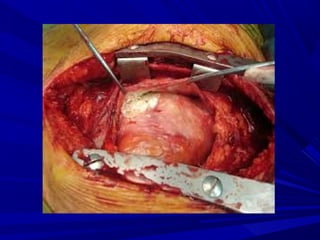

PERICARDIAL BIOPSYPERICARDIAL BIOPSY

No etiology for > 3 weeksNo etiology for > 3 weeks

3. SURGICAL TREATMENT3. SURGICAL TREATMENT

a)a) Surgical drainageSurgical drainage

b)b) PericardiectomyPericardiectomy